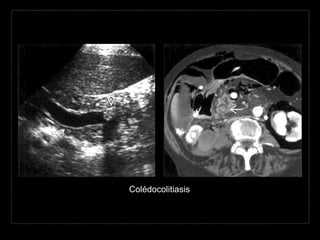

Colédocolitiasis